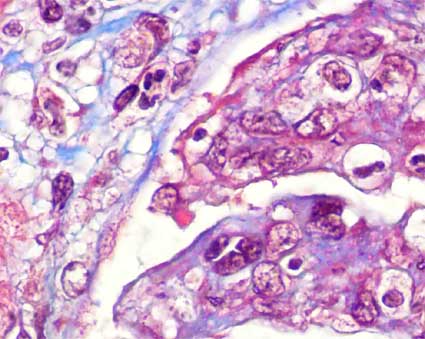

Figura 3.

Plata-metenamina, X400.